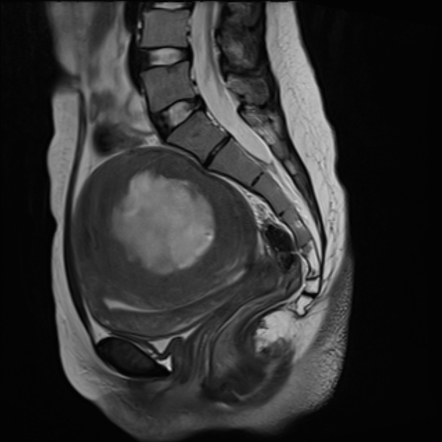

Uterine Leiomyomas | Radiology Case | Radiopaedia.org

uterine leiomyomas radiopaedia radiology t2

Myxoid Uterine Leiomyoma | Image | Radiopaedia.org

Uterine Leiomyosarcoma | Radiology Reference Article | Radiopaedia.org

leiomyosarcoma uterine radiopaedia leiomyoma radiology degenerated uterus

Myxoid Uterine Leiomyoma | Image | Radiopaedia.org

Myxoid Uterine Leiomyoma | Radiology Case | Radiopaedia.org

radiopaedia.org

radiopaedia.org

Myxoid leiomyosarcoma uterus. Myxoid leiomyosarcoma of the uterus. Pathology outlines